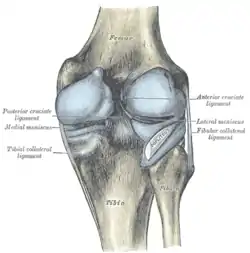

Intracapsular

The knee is stabilized by a pair of cruciate ligaments. These ligaments are both extrasynovial, intracapsular ligaments.[17] The anterior cruciate ligament (ACL) stretches from the lateral condyle of femur to the anterior intercondylar area.[13] The ACL is critically important because it prevents the tibia from being pushed too far anterior relative to the femur.[13] It is often torn during twisting or bending of the knee.[18] The posterior cruciate ligament (PCL) stretches from medial condyle of femur to the posterior intercondylar area. This ligament prevents posterior displacement of the tibia relative to the femur.[13] Injury to this ligament is uncommon but can occur as a direct result of forced trauma to the ligament.

The transverse ligament stretches from the lateral meniscus to the medial meniscus. It passes in front of the menisci. It is divided into several strips in 10% of cases.[10]: 208 The two menisci are attached to each other anteriorly by the ligament.[19] The posterior (of Wrisberg) and anterior meniscofemoral ligaments (of Humphrey) stretch from the posterior horn of the lateral meniscus to the medial femoral condyle. They pass anterior and posterior to the posterior cruciate ligament respectively.[13][10]: 208 The meniscotibial ligaments (or "coronary") stretches from inferior edges of the menisci to the periphery of the tibial plateaus.

Extracapsular

The patellar ligament connects the patella to the tuberosity of the tibia. It is also occasionally called the patellar tendon because there is no definite separation between the quadriceps tendon (which surrounds the patella) and the area connecting the patella to the tibia. [20] This very strong ligament helps give the patella its mechanical leverage [21] and also functions as a cap for the condyles of the femur. Laterally and medially to the patellar ligament the lateral and medial retinacula connect fibers from the vasti lateralis and medialis muscles to the tibia. Some fibers from the iliotibial tract radiate into the lateral retinaculum and the medial retinaculum receives some transverse fibers arising on the medial femoral epicondyle.[10]: 206

The medial collateral ligament (MCL a.k.a. "tibial") stretches from the medial epicondyle of the femur to the medial tibial condyle. It is composed of three groups of fibers, one stretching between the two bones, and two fused with the medial meniscus. The MCL is partly covered by the pes anserinus and the tendon of the semimembranosus passes under it.[10]: 206 It protects the medial side of the knee from being bent open by a stress applied to the lateral side of the knee (a valgus force).[10]: 206

The lateral collateral ligament (LCL a.k.a. "fibular") stretches from the lateral epicondyle of the femur to the head of fibula. It is separate from both the joint capsule and the lateral meniscus.[10]: 206 It protects the lateral side from an inside bending force (a varus force). The anterolateral ligament (ALL) is situated in front of the LCL.

Left knee-joint from behind, showing interior ligaments.